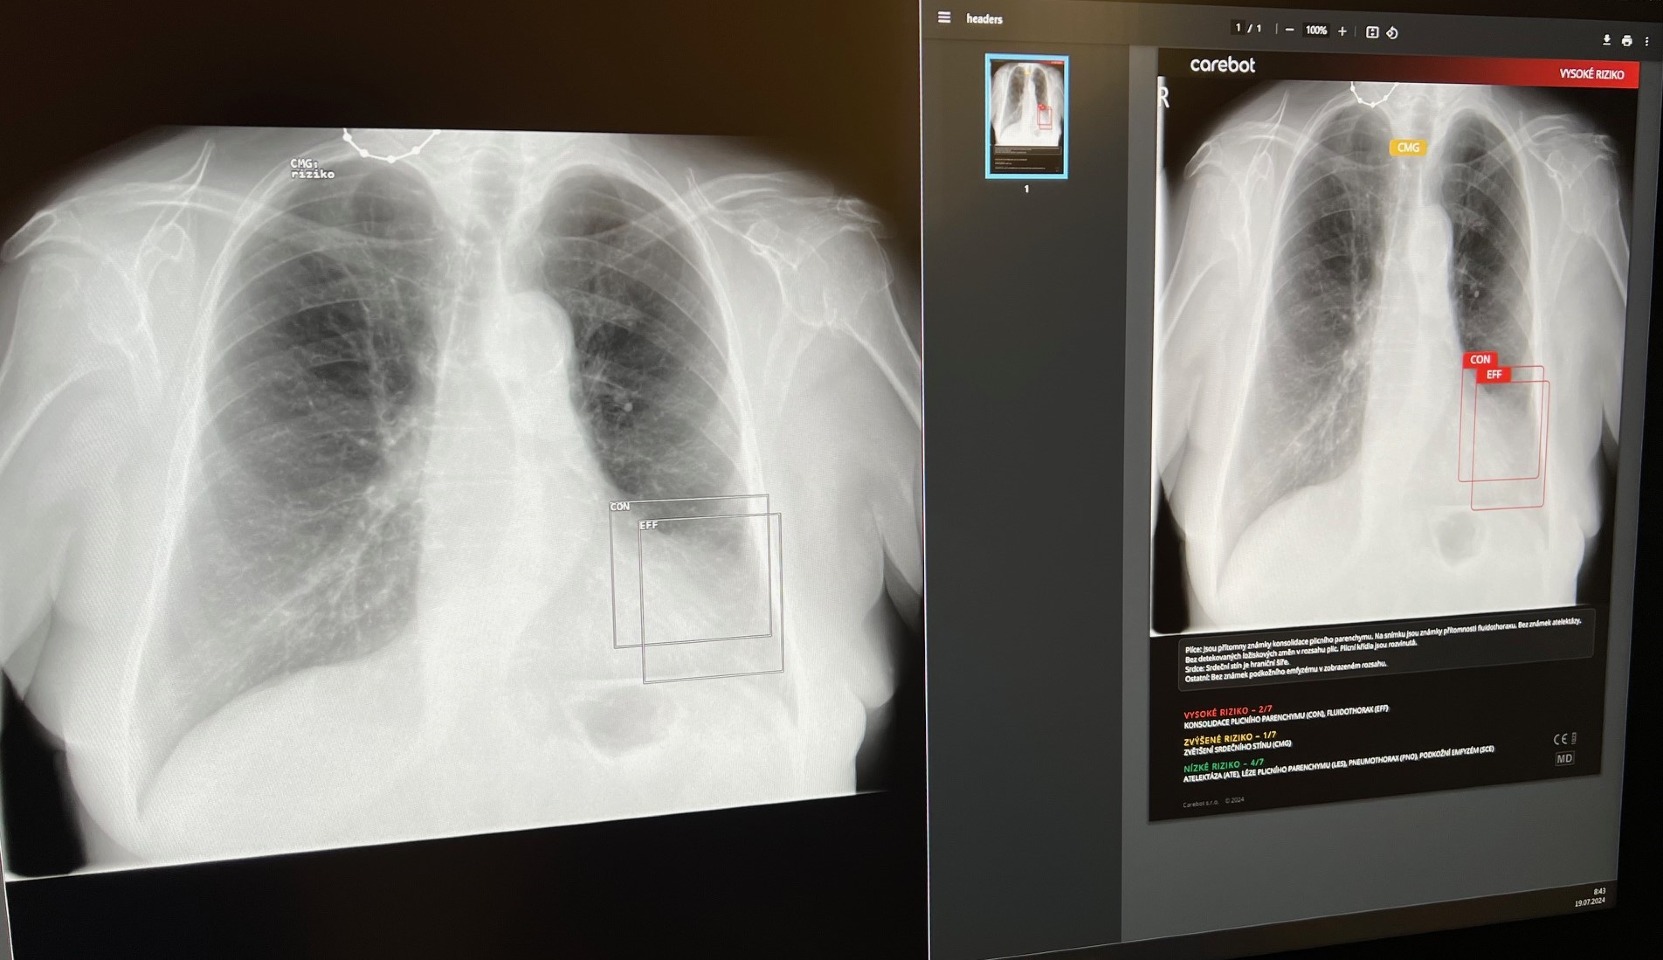

Umělá inteligence (AI) přináší revoluční změny do medicíny. V posledních letech se stává klíčovým faktorem v diagnostice a léčbě nemocí. Jedním z příkladů, jak AI mění zdravotnickou praxi, je systém CARE BOT, který se testuje i na radiologickém oddělení v Nemocnici Tábor, a.s. Představme si, jaké jsou jeho hlavní výhody a jaký dopad má na péči o pacienty.

CARE BOT: Pomocník radiologů

CARE BOT, je český projekt, který využívá AI k analýze rentgenových snímků plic. Jeho hlavním cílem je urychlit diagnostiku a zlepšit péči o pacienty. Díky pokročilým algoritmům dokáže CARE BOT rychle identifikovat patologie, jakou jsou nádory, záněty nebo plicní onemocnění. Lékaři mohou lépe plánovat léčbu a minimalizovat lidské chyby. Pro pacienty to znamená větší šanci, že se onemocnění rozpozná včas a zahájí se správná léčba. Počet radiologických vyšetření neustále roste, ale počet lékařů zůstává téměř stejný. Umělá inteligence je proto žádaným partnerem, díky kterému bude lékař schopen zvládnout velký počet vyšetření v požadované kvalitě.